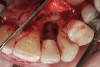

The main biological consideration with cement-retained implant restorations is the vulnerability of peri-implant tissues. Cement contamination readily occurs around implant sites for many reasons. First, as previously mentioned, the soft tissues are much more delicate and vulnerable to tearing when using protection techniques such as retraction cord placement, which is, therefore, contraindicated.16 Cord placement has been shown to strip the weak hemidesmosomal attachment and provide a pathway along the side of the implant for cement extrusion to occur (Figure 1 and Figure 2).17

Figure 1

Figure 2